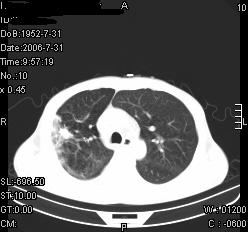

患者,男,54岁,咳嗦,咳痰20天。抗炎治疗2周。现esr76mm/h,目前患者症状明显好转,但发现两次ct片未见明显变化。两次分别做与7.25、7.31。第一次诊断右肺上叶炎症累计胸膜。大家看,从影像上内排除结核吗?

结核的可能性非常大,右上肺病变应该考虑干酪性肺炎。理由:

1.纵隔内多发淋巴结肿大。

2.esr76mm/h。

3.虽经抗炎治疗肺窗病灶有所吸收、减小,但纵隔窗病灶形态、密度、范围无明显变化。如果是单纯的大叶性肺炎,“抗炎治疗2周,目前患者症状明显好转”病灶应该基本消散了,至少也处于吸收消散期,密度变淡、范围变小。同时本病例所示其内的密度不均匀,见多发大小不一空洞样影也不符合大叶性肺炎吸收消散期表现。

病灶特点:片状 索条 结节混杂影,部分融合,密度不均,广泛累及相应胸膜.

临床治疗;二周未吸收.但症状好转.

多考虑:肺结核.